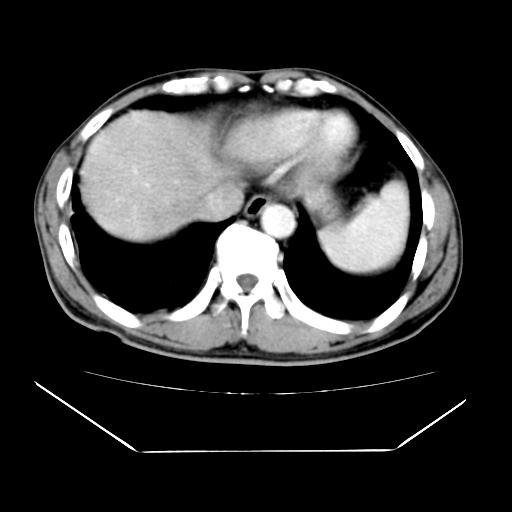

男性,55岁,外院体检afp明显升高,但b超未发现异常,否认乙肝病史。来我院ct增强。有延时扫描。

延时扫描完全充填,血管瘤

肝脏右叶动脉期可见低密度影,至延迟期被充填,考虑血管瘤可能性大。

不排除肝右叶肝癌可能。

如果这个是癌灶的话则下腔静脉有瘤栓可能

肝6段血管瘤

血管瘤可能性大。

考虑肝右静脉影。